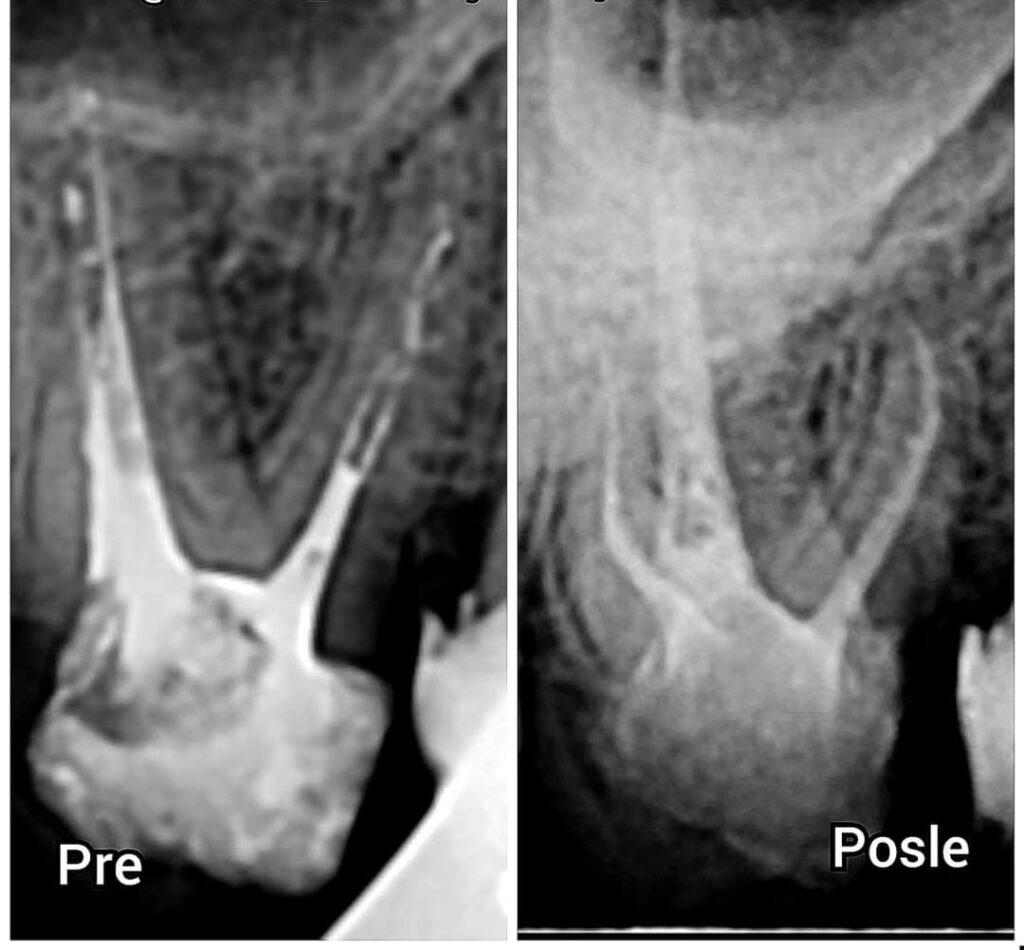

Kako bi lečenje zuba uspelo, potrebno je prvo otvoriti zub i izvršiti vađenje inficiranog živaca iz zuba (pulpu zuba), očistiti kanal/e korena zuba i na kraju očišćeni kanal napuniti posebnim biokompatibilnim materijalom. Nakon što se kanali napune najčešće se postavlja bela plomba ,ali ako je veći deo zuba zahvaćen karijesom i plomba ne bi mogla da stoji, tada se izrađuje protetska nadoknada poput inleja, onleja ili overleja, a u nekim slučajevima potrebno je izraditi i zubnu krunicu.

Kako bi se sprečila instrumentacija preko vrha korena, koriste se digitalni merači dužine kanala korena, tzv. apex lokatori u kombinaciji sa rentgenskim snimcima.Ponekad vađenje živca iz zuba ne može biti uspešno izvedeno zbog tankih, krivudavih i neprohodnih korenskih kanala, pređašnjih loših endodontskih zahvata i sl. Neki od takvih slučajeva uspešno se rešavaju apikotomijom (hirurškim uklanjanjem vrha korena zuba).

Ako nakon endodontskog lečenja zuba upala i dalje traje, verovatno se radi o kanalu korena zuba koji je jako zakrivljen ili teško prohodan u svom. Taj završni deo kanala nije moguće adekvatno endodontski tretirati tj. nije moguće vađenje živca iz zuba u potpunosti i on je najčešći uzrok neuspeha lečenja. Stoga se apikotomijom odstranjuje vrh korena, a kanal se na mestu presecanja korena ispunjava materijalom koji dobro zaptiva. Tako se apikotomijom odstranjuju problematični delovi korena, a postavljanjem ispuna na ostatak korena sprečava se prodor mikroorganizama iz korenskog kanala u područje oko vrha korena zuba. Ovaj hirurški zahvat je kratak, a komplikacije su retke. Nakon lokalne anestezije napravi se rez na gingivi (zubnom mesu), a potom se na kosti izradi otvor kroz koji se pristupa vrhu korena.

Odstrani se nekoliko milimetara vrha korena, a na preostali deo se postavi ispun. Gingiva se postavlja preko otvora u kosti i ušije u području reza. Šavovi se skidaju nakon 5 – 7 dana, gingiva srasta, a kost se obnovi i ispuni preostali defekt.